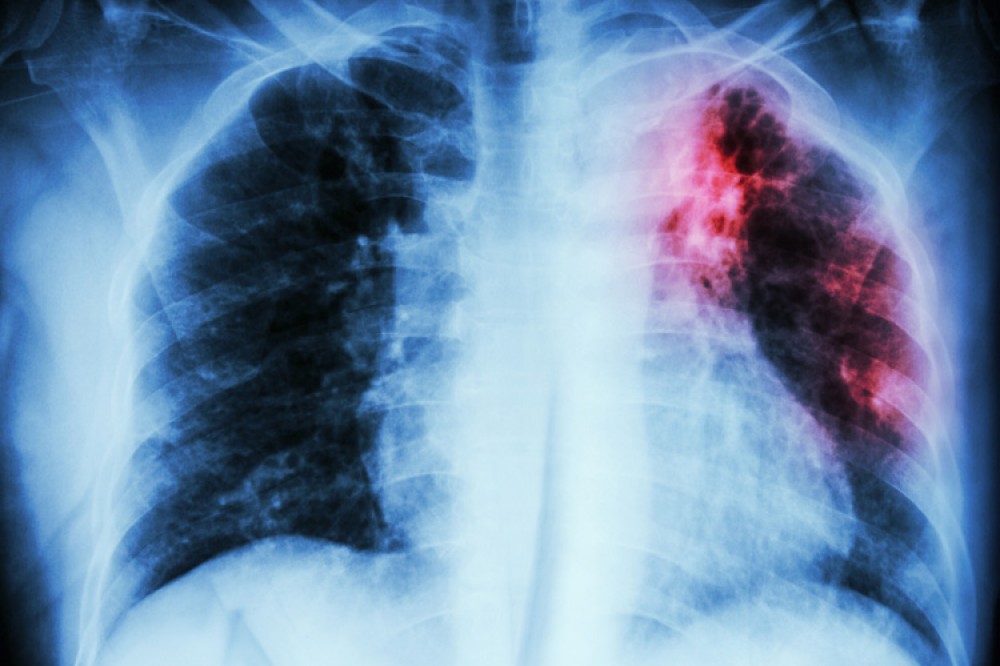

Azərbaycanda vərəmə yoluxma sayı azalmaqdadır

Azərbaycanda vərəmə yoluxma sayı azalmaqdadır.

Onun sözlərinə görə, hazırda vərəmə həm yoluxma, həm də ölüm hallarında azalma müşahidə edilir:

“Lakin təəssüf ki, vərəm hələ də cəmiyyətdə qorxu və yanlış inanclar doğuran xəstəliklərdəndir. Xəstə olduğu otaq gündə bir neçə dəfə açıq havaya verilməlidir. Xəstə öskürərkən, maskadan istifadə etməli, ünsiyyət zamanı 1–2 metr məsafə saxlamaq tövsiyə olunur. Qeyd edim ki, günəş şüaları vərəm mikrobunu öldürür. Ona görə də, otağın işıqlı və təmiz olması çox vacibdir”.